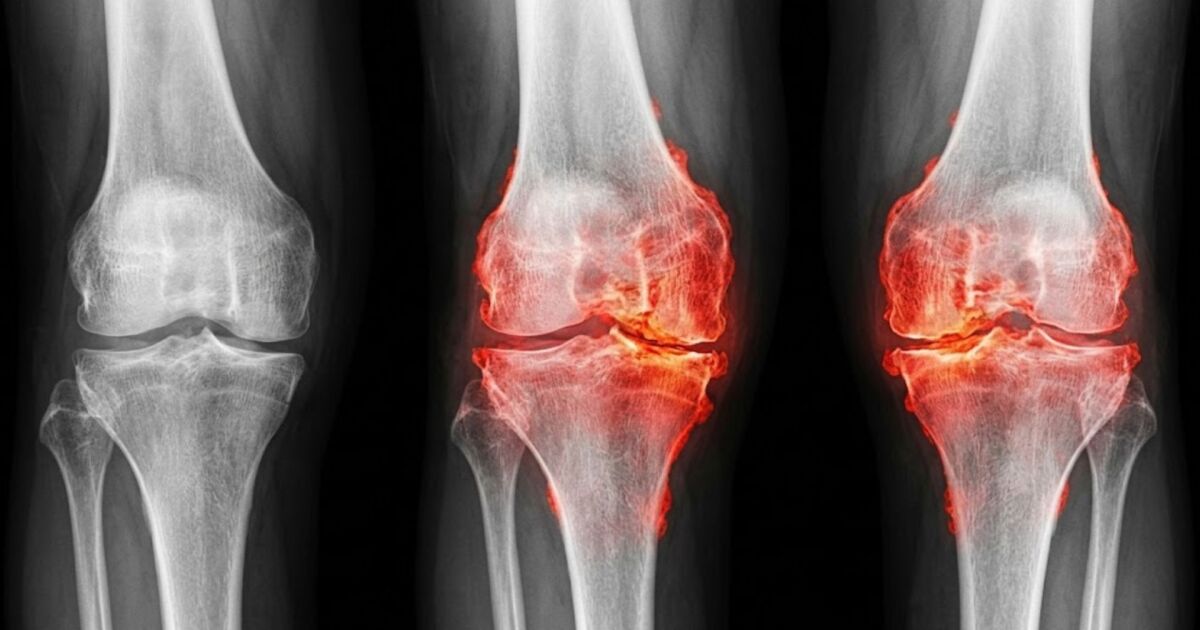

Износването на ставите засяга милиони хора по света и често води до силна болка, ограничена подвижност и в крайна сметка смяна на коляното или тазобедрената става.

Изследователите от Станфорд проверяват дали именно този протеин участва в развитието на остеоартрита, заболяването, при което продължителното натоварване води до разрушаване на колагена в хрущяла, възпаление на ставите и хронична болка.